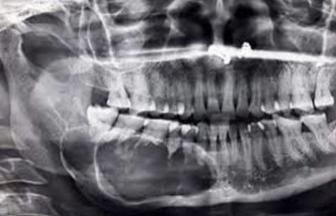

Give a differential diagnosis for the following radiographic image:

(multilocular radiolucency in right posterior mandible)

A

1. Odontogenic keratocyst

2. ameloblastoma

3. central giant cell granuloma